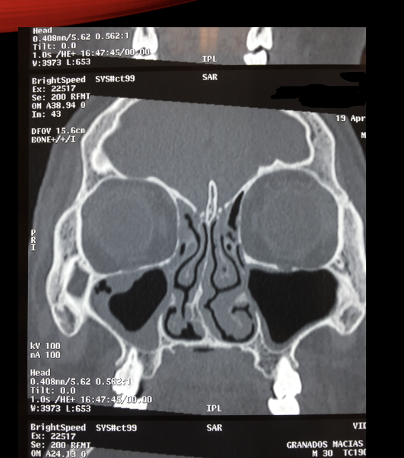

A

Posterior porque no hay crista gali, etmoides posterior

Afectado seno maxilar izq, derecho. Imagen ocupación 50%, homogéneo, de superficie convexa. Mucocele porque es convexo. Sinusitis maxilar BL. Hay sinusitis etmpdodal. Para que etmpides esté sano debemos de ver trabeculas del hueso super flaquitas.

Si se ve engrosado es sinusitis etmoidal

Sinusitis maxiloetmoidal bl con posible presencia de mucocele o quiste de retención de lado derecho.